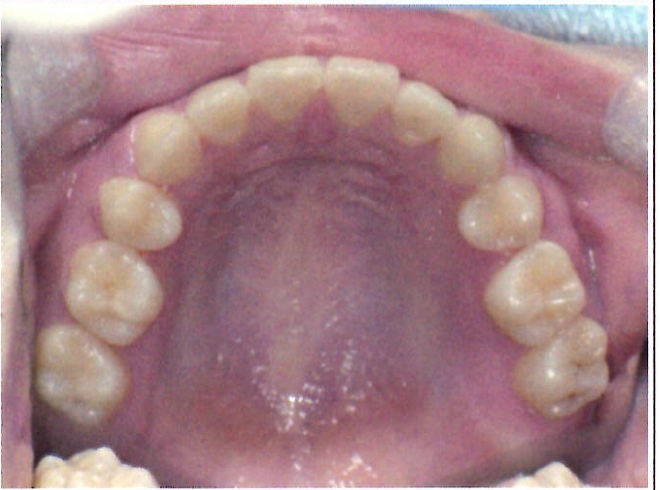

| 主訴・治療前の状態 | 過蓋咬合(噛み合わせが深く、下の前歯が見えない状態)により歯ぎしりができない状態でした。また、上下顎前歯部に叢生(クラウディング・ガタガタ)がありました。 |

| 治療内容 | 矯正治療により、過蓋咬合と上下の叢生を改善しました。 |

| 治療結果 | 適切な被蓋(上下の前歯の重なり)が得られ、下の前歯がきちんと見えるようになりました。上下の前歯の歯並びも美しく整い、しっかりと噛み合うようになりました。機能面・審美面ともに大きく改善した症例です。 |